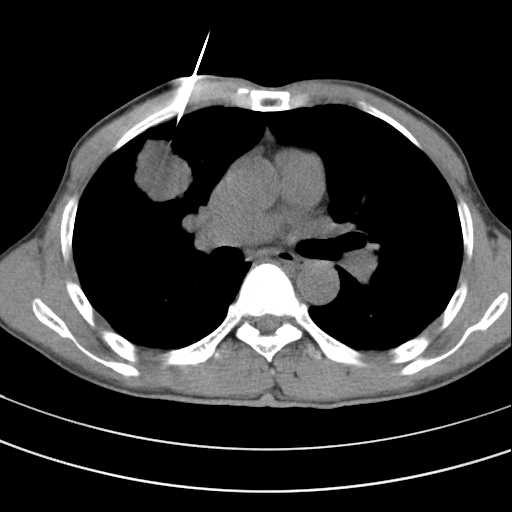

Chẩn đoán hình ảnh trong UNG THƯ PHỔI

Bài giảng Chẩn đoán hình ảnh trong UNG THƯ PHỔI from TRAN Bach